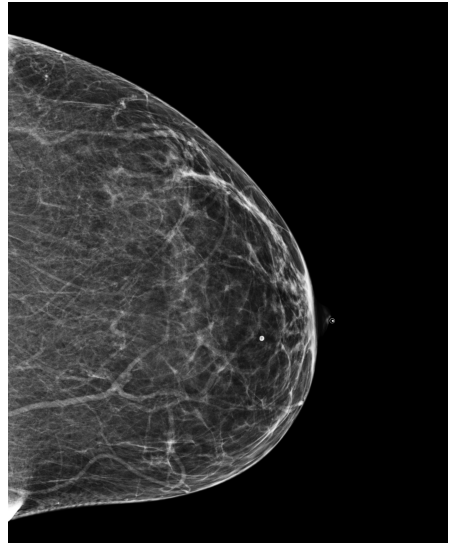

Refer to caption

(a) FeatAlign

(b) FeatAlignReg

(c) ImgFeatAlign/ImgAlign

(d) FeatAlign

(e) FeatAlignReg